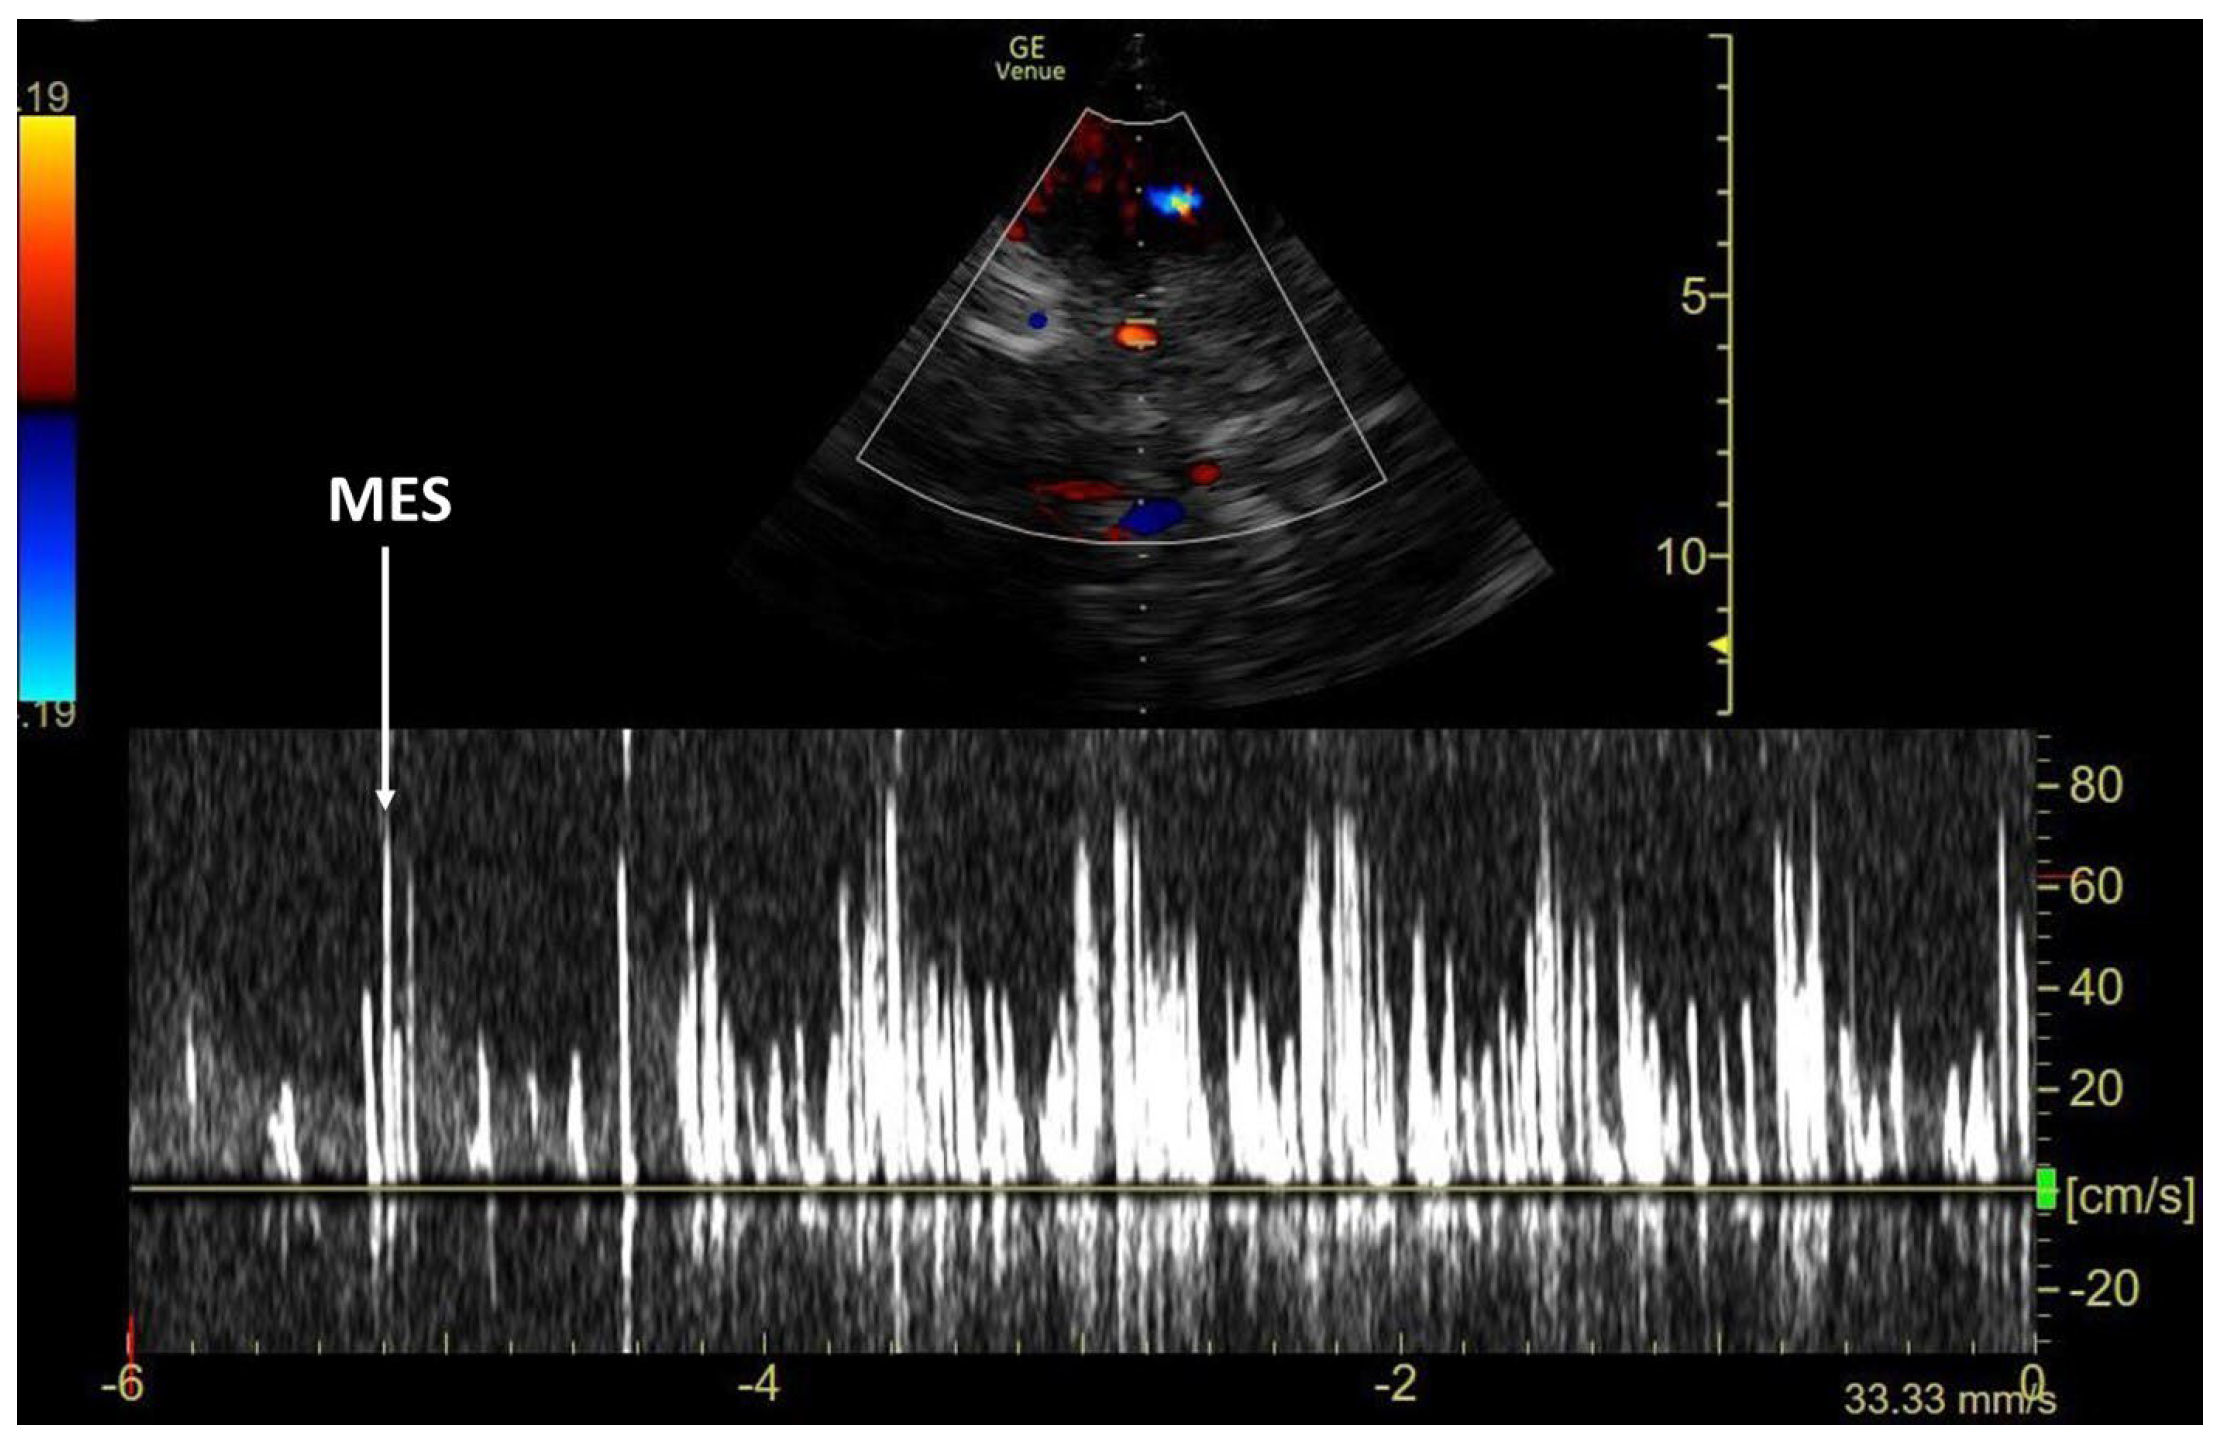

3.1. TCCD MES-Positive Case 1

| MES | microembolic signals |

| TCCD | Transcranial–ecocolor Doppler |